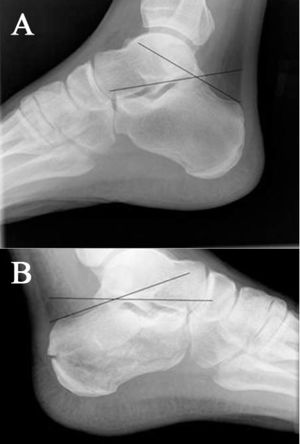

- Decreased Boehler's angle (<25') may be only sign of fracture (compare with opposite side)